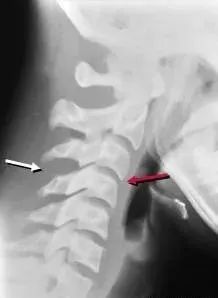

十、单侧小关节交锁

通常由屈曲性或过伸性旋转暴力导致,30%伴有神经性损伤,侧位片表现为椎体向倾斜移位,正位片可见棘突投影不在一条轴线上。